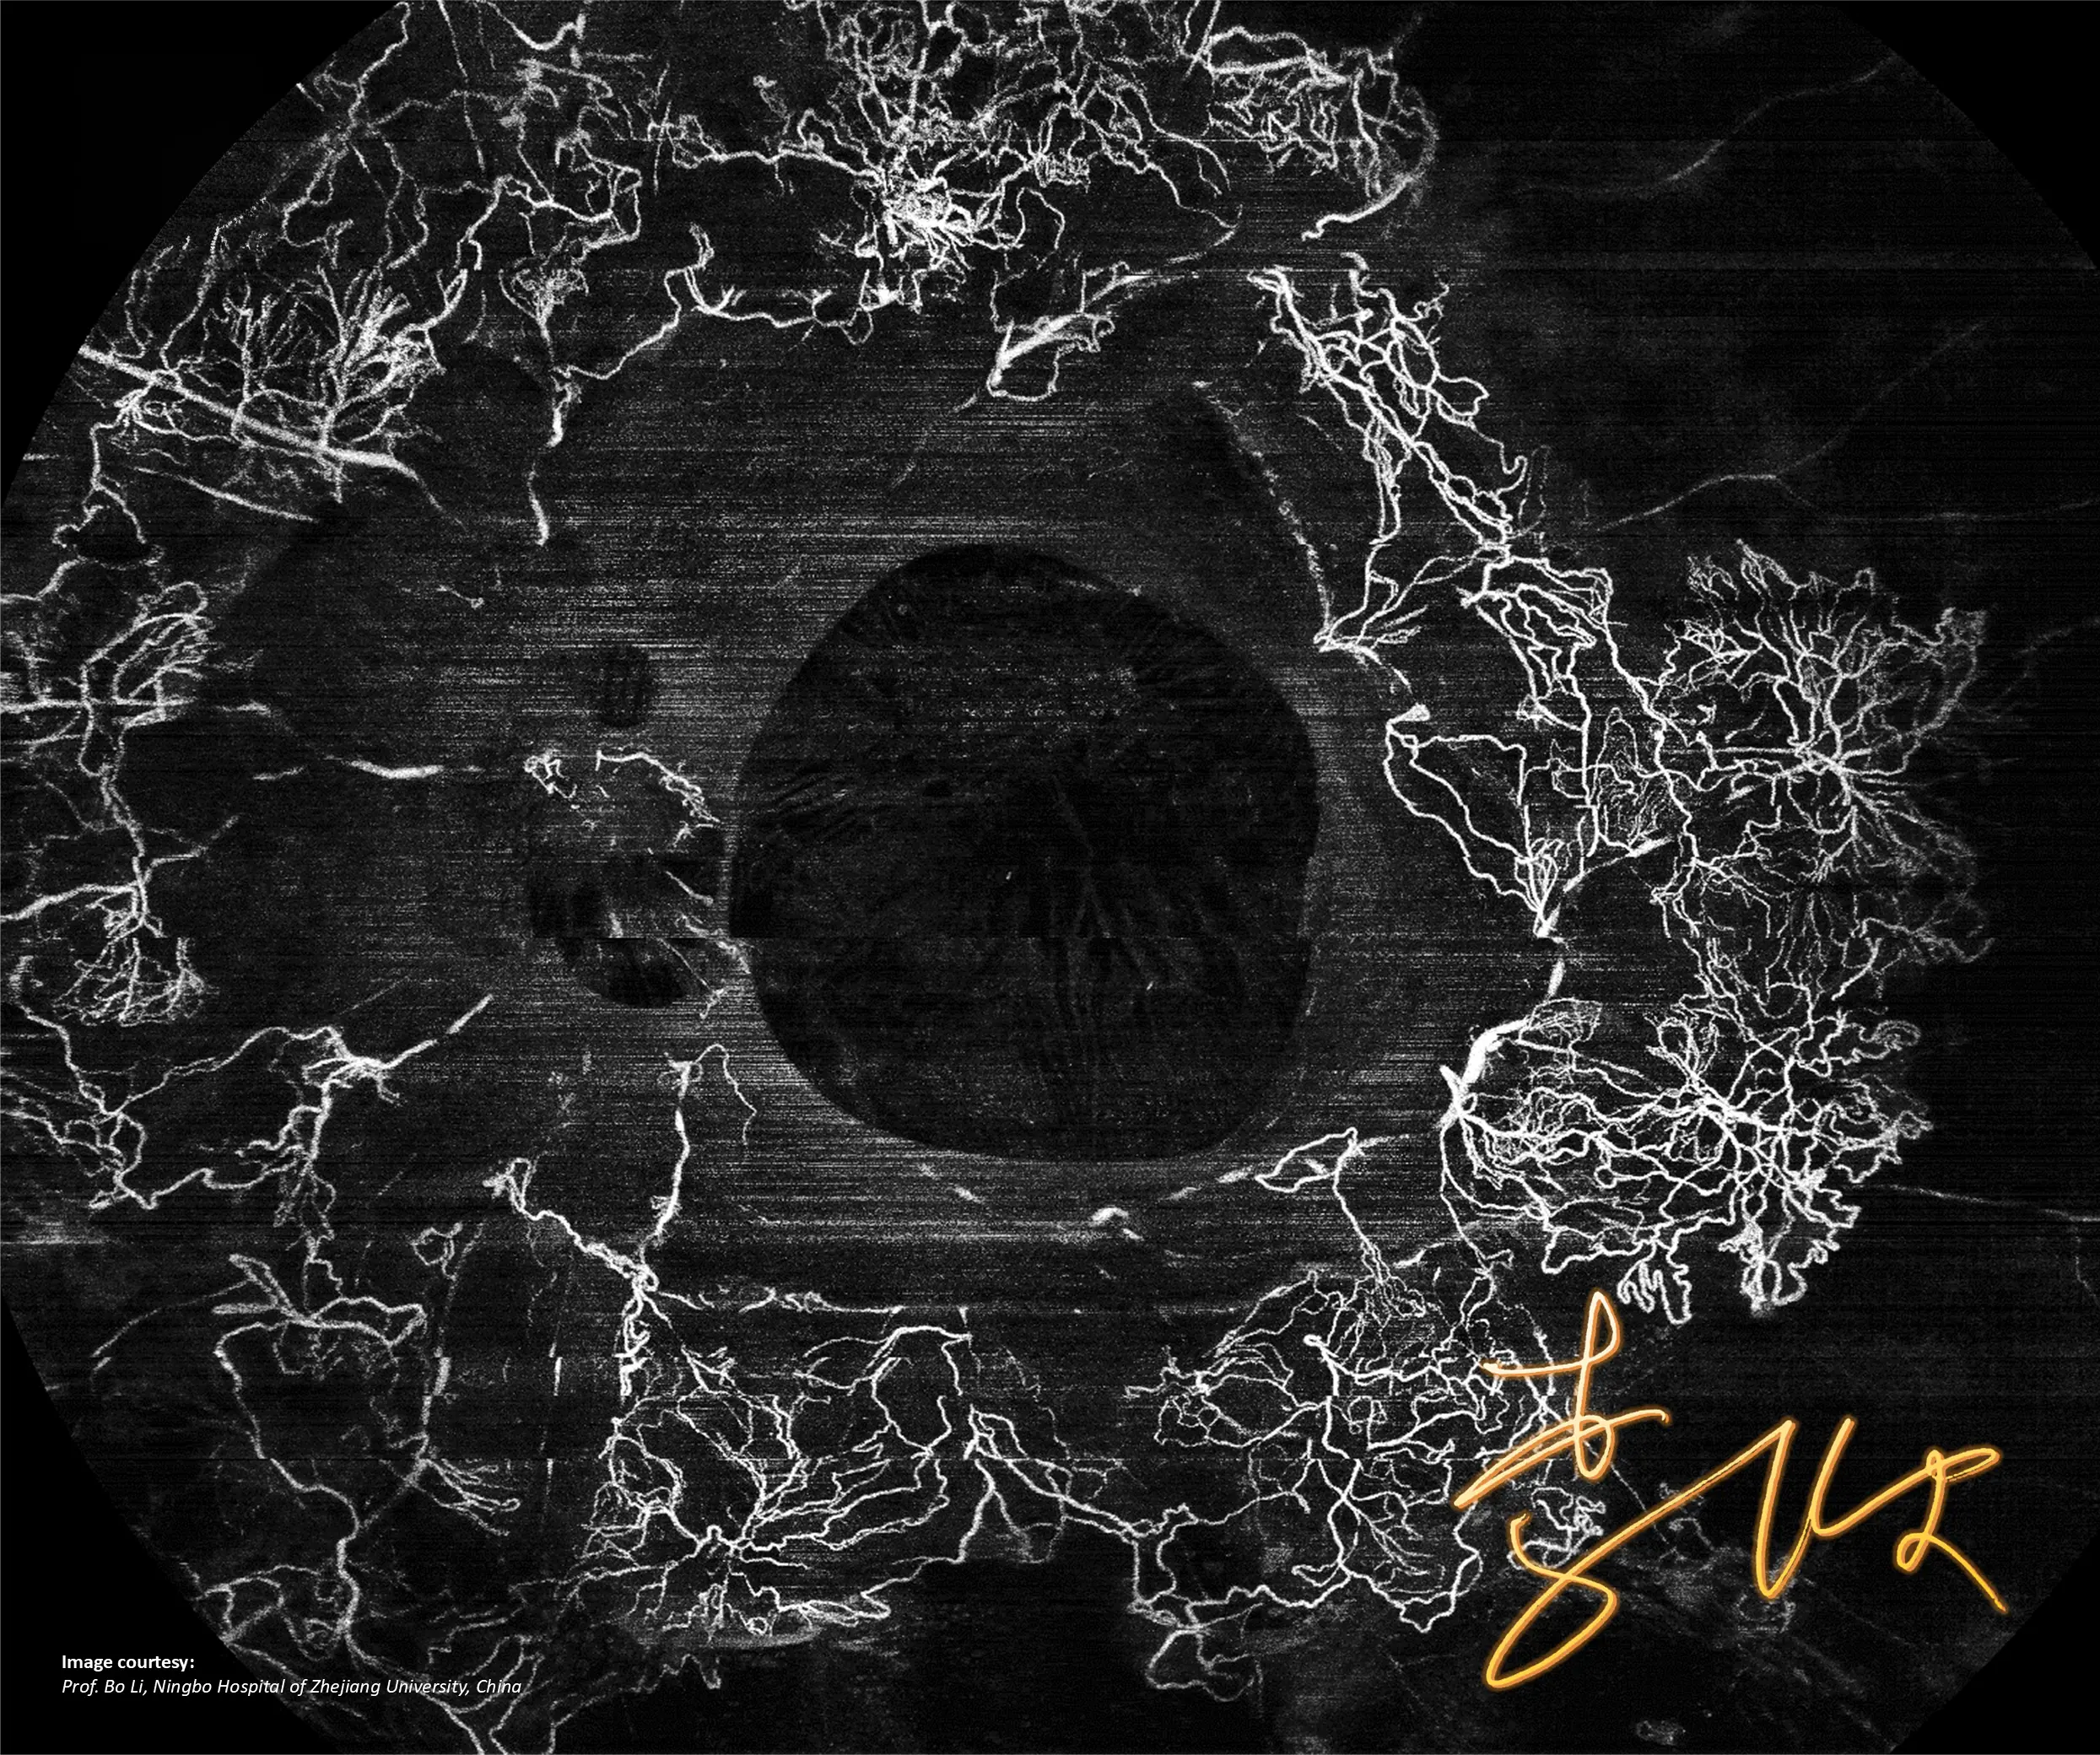

NIEZRÓWNANA JAKOŚĆ OBRAZOWANIA

Pełna diagnostyka

w jednym ujęciu

GALERIA PRZYPADKÓW

Kliniczne znaczenie

innowacji